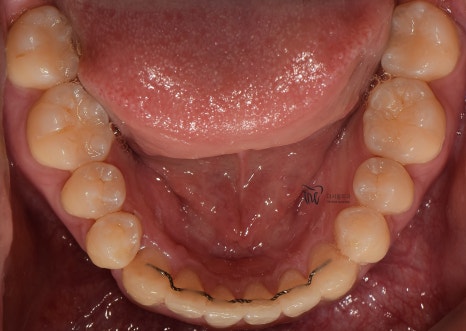

『1년만에, f.u』

근데..ㅋㅋㅋ 보통 3개월에 한번씩 정기검진을

받으러 오셔라는 안내를 드리게 되는데 이 분은

13개월만에.. 즉.. 거의 1년만에 치과에 오셔서

상태 점검을 받으셨습니다.

다행이였던 것은, 교정유지기 가

잘 붙어있었다는거.

게다가, 양치질이나 치실 사용 등

구강 위생 관리에 철저하셨던 분입니다.

자주 안 오신건, 어찌보면 아쉬운점이긴 한데

결과만 놓고 봤을 때는 손색이 없네요.

치석도 거의 없으면서 충치들도 없습니다.